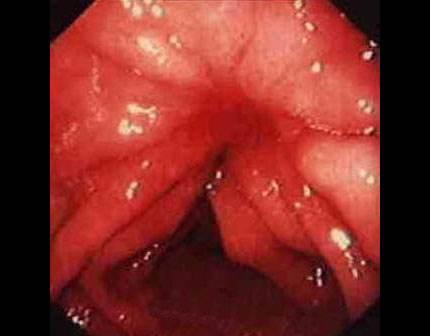

摘要:痔瘡癌變是嚴(yán)重的健康問(wèn)題,其前兆包括便血、疼痛、肛門(mén)不適、排便習(xí)慣改變等10個(gè)跡象。了解并識(shí)別這些前兆的重要性在于早期發(fā)現(xiàn)、診斷和治療,以提高治愈率和生存率。對(duì)于痔瘡患者,密切觀察并及時(shí)就診是預(yù)防癌變的關(guān)鍵。

痔瘡癌變的10個(gè)前兆

1、痔瘡疼痛加劇:痔瘡患者如感覺(jué)疼痛逐漸加劇,可能是癌變的一個(gè)信號(hào)。

2、痔瘡出血:長(zhǎng)期痔瘡出血,尤其是出現(xiàn)持續(xù)性出血時(shí),應(yīng)警惕癌變的可能。

3、痔瘡體積變化:如痔瘡體積在短時(shí)間內(nèi)迅速增大,可能是癌變的征兆。

4、排便習(xí)慣改變:如排便頻率增加或減少,以及出現(xiàn)便秘與腹瀉交替的情況,可能與痔瘡癌變有關(guān)。

5、肛門(mén)不適:出現(xiàn)肛門(mén)墜脹、異物感等癥狀時(shí),應(yīng)考慮痔瘡癌變的可能性。

6、消瘦和乏力:如體重迅速下降、乏力等全身癥狀出現(xiàn)時(shí),可能是痔瘡癌變的警示信號(hào)。

7、淋巴結(jié)腫大:如出現(xiàn)腹股溝或盆腔淋巴結(jié)腫大,可能與痔瘡癌變有關(guān)。

8、食欲減退:長(zhǎng)期食欲減退,尤其是伴有上述癥狀時(shí),應(yīng)警惕痔瘡癌變。

9、肛周瘙癢:肛周瘙癢可能是痔瘡炎癥的表現(xiàn),長(zhǎng)期不緩解可能發(fā)展為癌變。

10、便血顏色變化:如便血顏色由鮮紅色變?yōu)榘导t色或混合有黏液,應(yīng)引起重視。